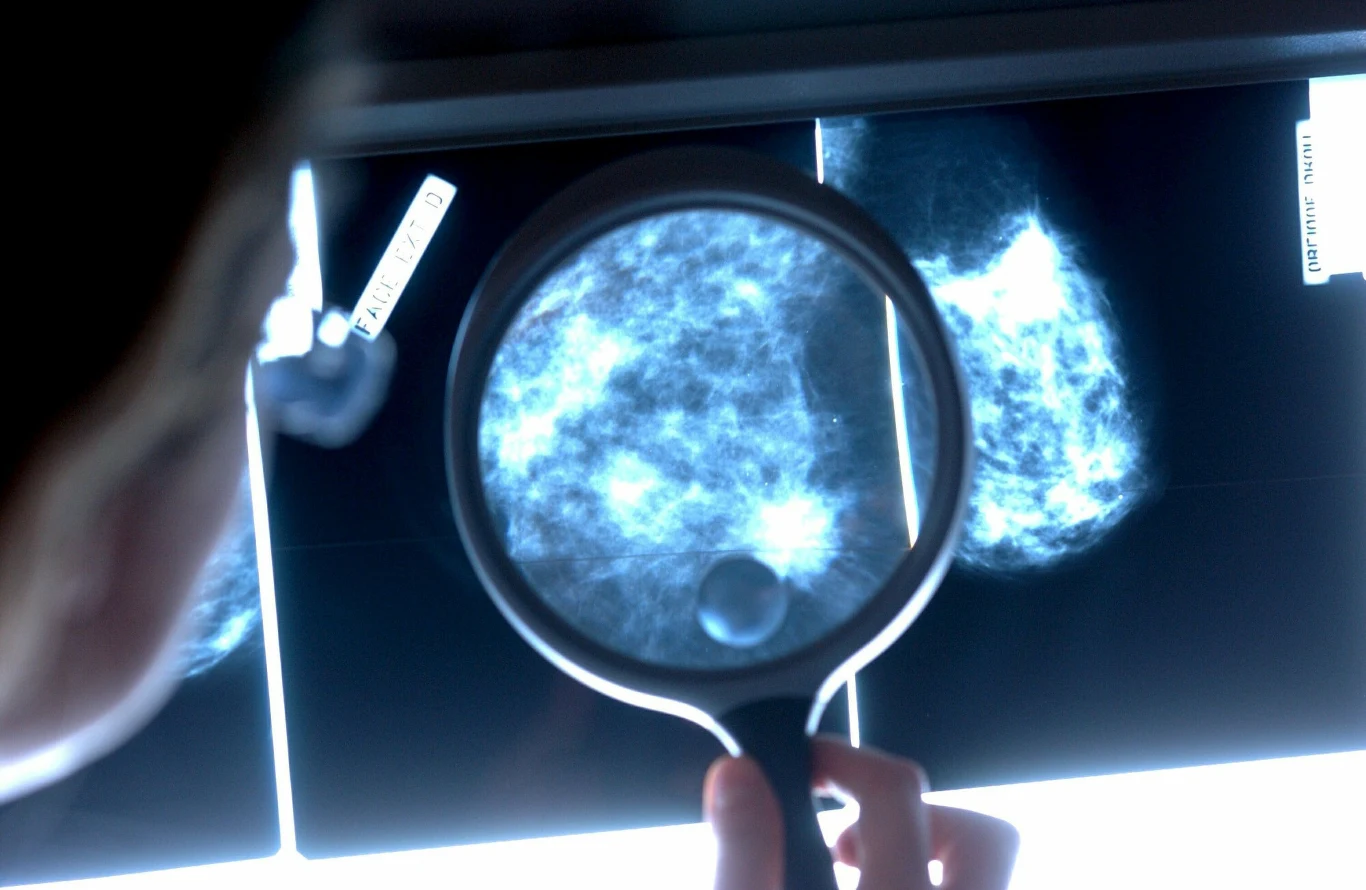

Mammografia szansą na dłuższe życie

Uczestnictwo w badaniach przesiewowych wykrywających raka piesi, które wprowadziła już większość rozwiniętych krajów, w tym Polska, powinno sięgać minimum 70 proc. docelowej populacji. Tymczasem w naszym kraju frekwencja wynosi jedynie niecałe 40 proc. W ostatnich latach (również ze względu na pandemię COVID-19) statystyki są jeszcze gorsze. Specjaliści są jednogłośni - uważają, że dzięki badaniom, u kobiet diagnozowano by zdecydowanie mniej raków zaawansowanych.

Bezpłatna mammografia dla kobiet

Każda kobieta między 50. A 69 rokiem życia powinna wykonać badanie mammograficzne raz na dwa lata. Takie badanie jest w Polsce refundowane i zupełnie darmowe. Specjaliści przekonują, że to dobrodziejstwo dzisiejszych czasów - wykonywanie mammografii zmniejsza bowiem ryzyko zgonu z powodu raka o 30-40 proc.

Ryzyko zachorowania na raka piersi wzrasta z wiekiem, ponadto wcześnie wykryty lepiej i skuteczniej się leczy. Profilaktycznie dobrze też wykonać badanie genetycznej najczęstszych mutacji związanych z rakiem piersi i jajnika.